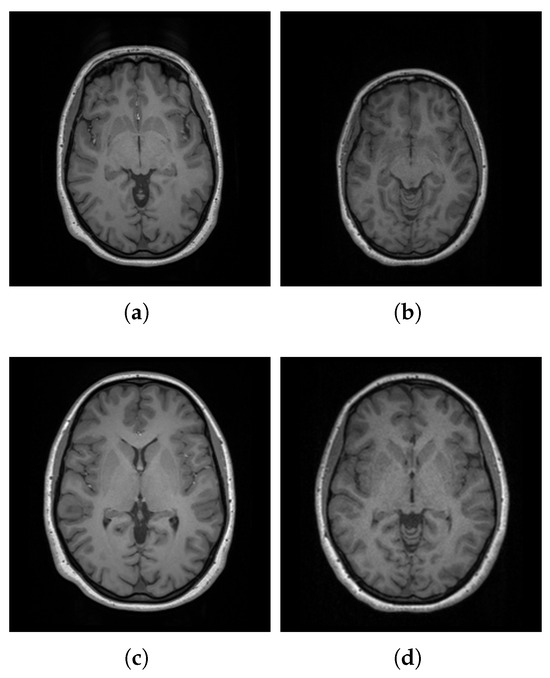

3.2. Preprocessing

3.2.1. Spatial Normalization

3.2.2. Bias Field Correction

3.2.3. Denoising

3.2.4. Brain Extraction

3.2.5. Intensity Normalization